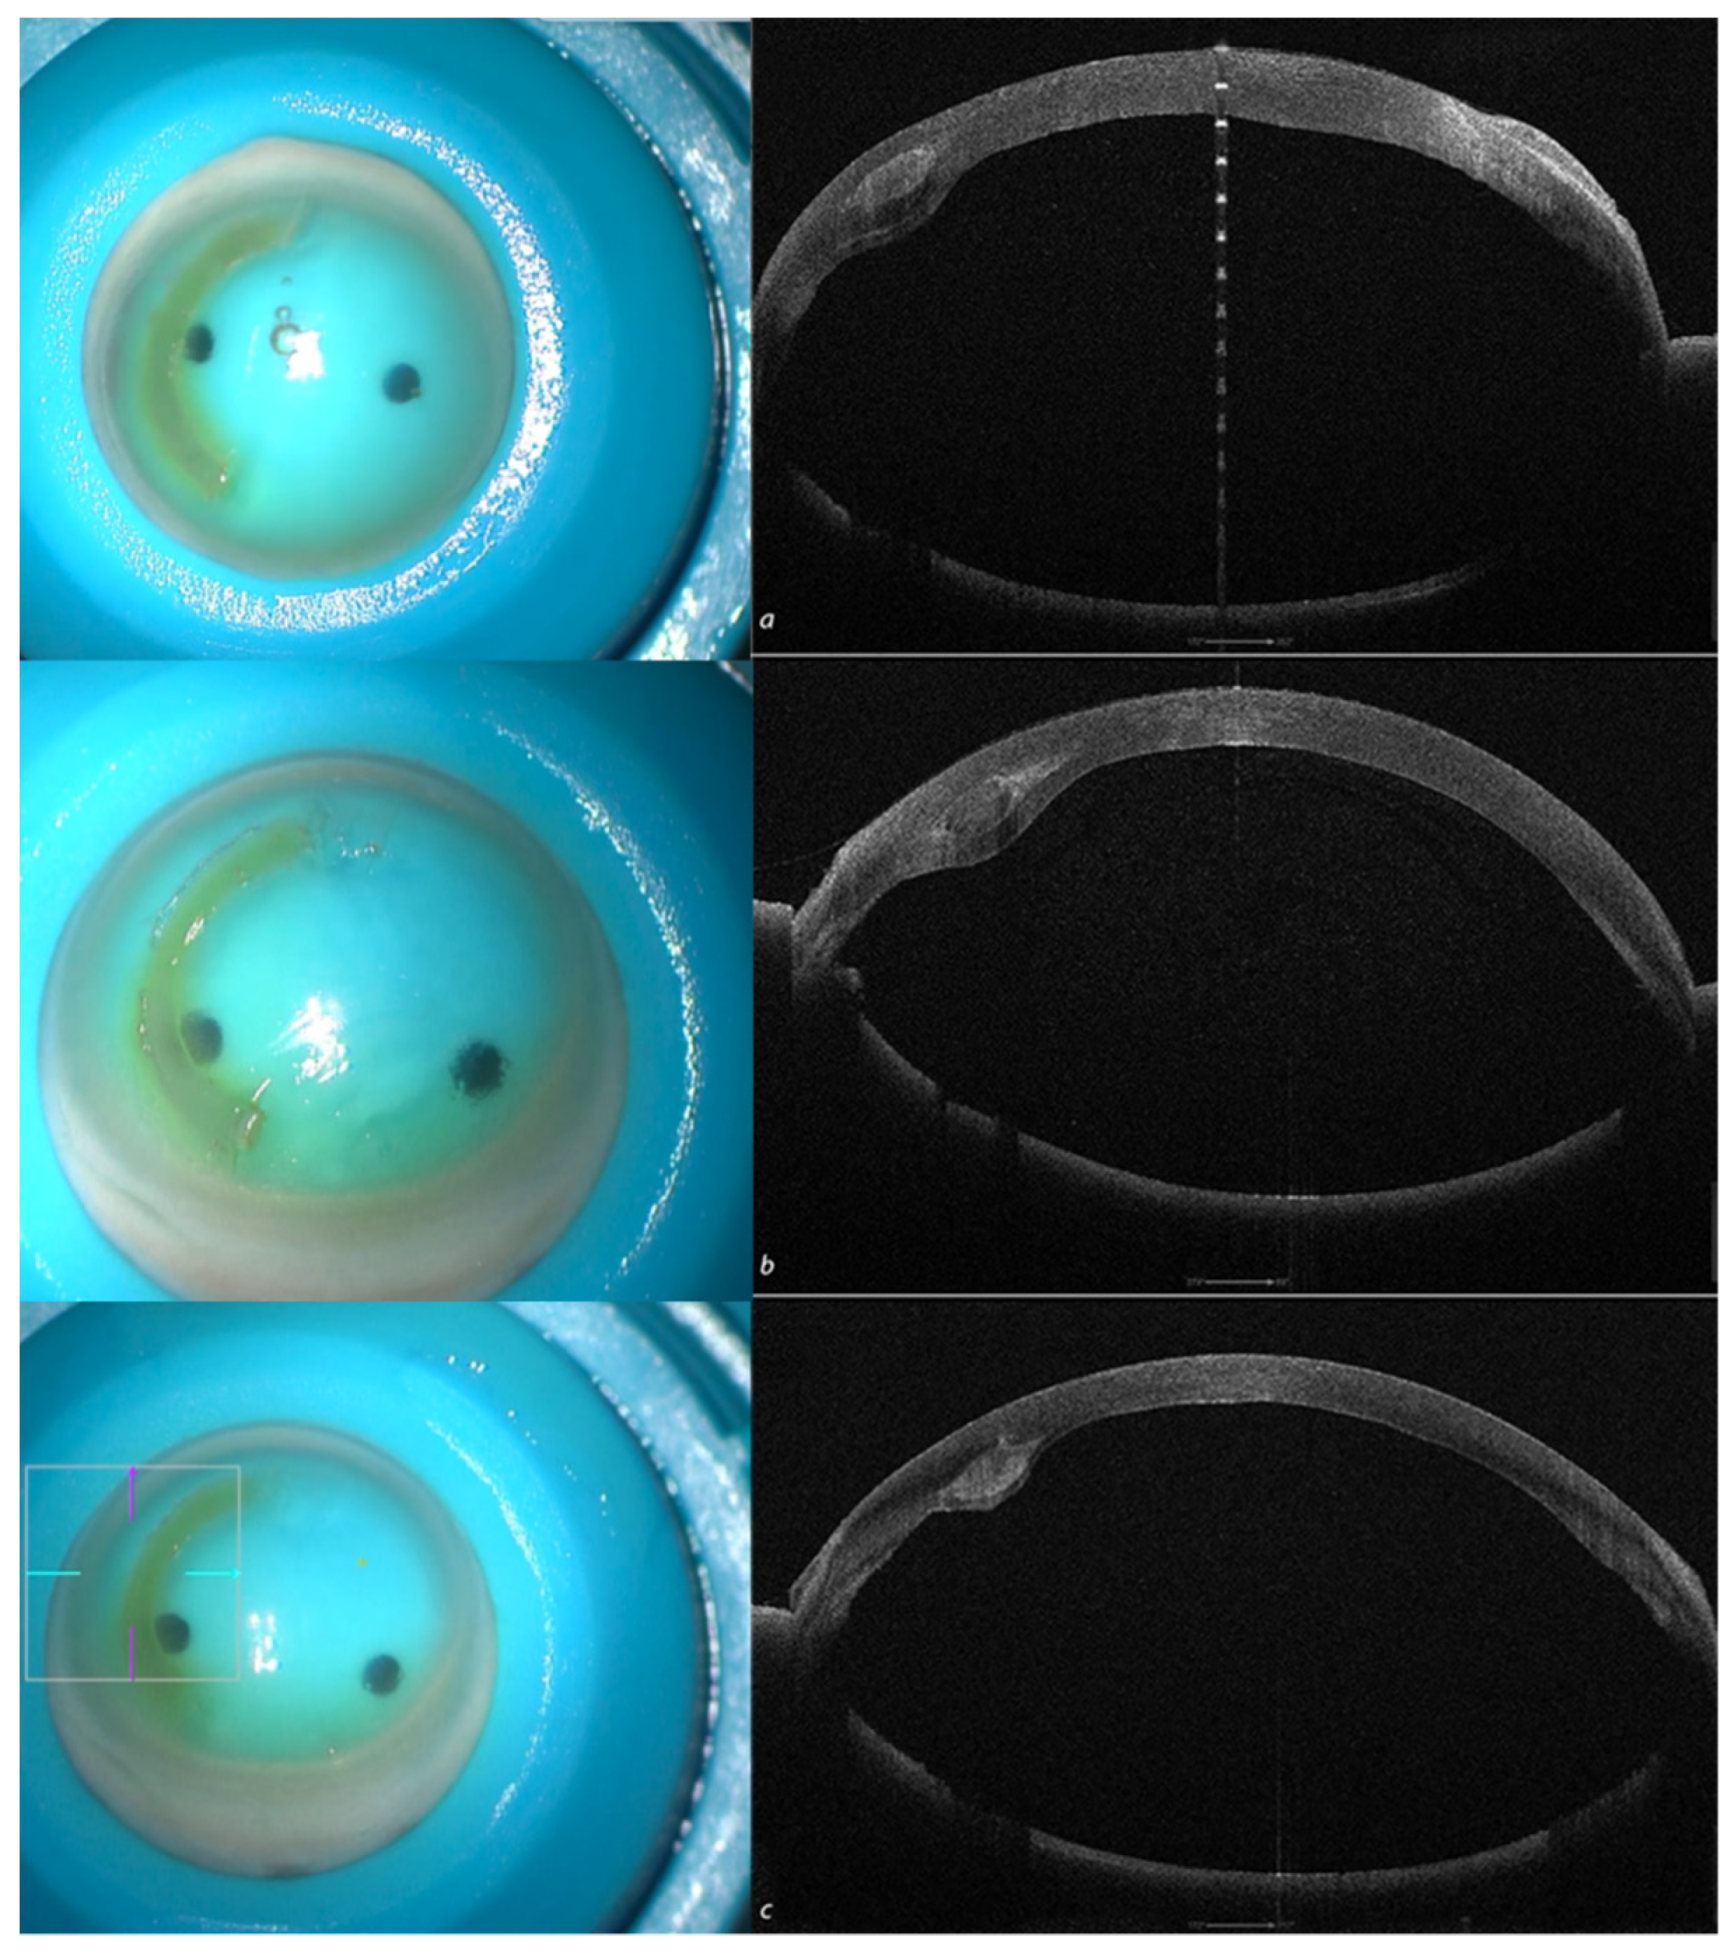

2.3.1. Patient 1: Single ACXL CAIRS Implant